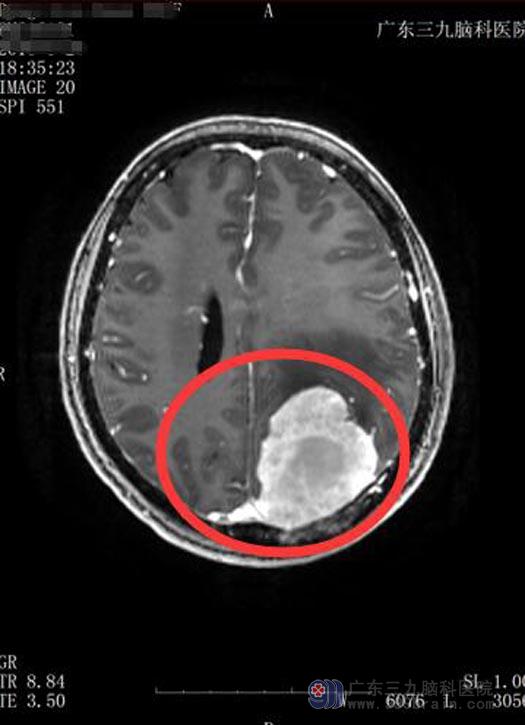

半年前,她除了头晕,还出现有阵发性的头痛,双眼看东西开始模糊,这让原本视力很好的李阿姨着急了。在儿子和老伴的陪同下辗转当地多家医院检查,结果都是左侧顶叶占位,考虑胶质瘤。这让他们陷入惊恐,恶性肿瘤,他们不愿面对、不敢面对,也不得不面对。

带着一点怀疑,他们来到广东三九脑科医院综合神经外科,再次做了核磁共振检查,鲁明主任将前后检查的片子作了仔细的对比和鉴别,觉得脑膜瘤的可能性更大一些。完善术前检查后,由鲁明主任主刀行左侧顶枕部脑膜瘤切除术,手术十分顺利,术后病理提示:过渡性脑膜瘤,WH0Ⅰ级。

▲手术前MR